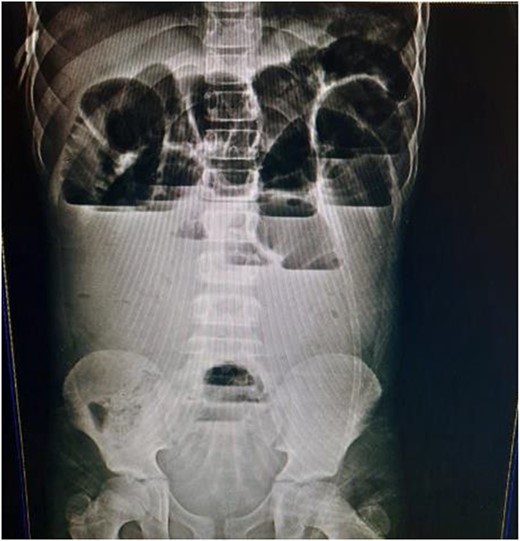

A 9-year-old child presented at the emergency department at our hospital after 4 days with symptoms of small bowel obstruction, including diffuse abdominal pain, nausea, vomiting, constipation and abdominal distension. His past medical history was not significant, and he had no surgical history. The abdomen was breathing, smooth, tender without rebound tenderness; no signs of peritonitis and appendicitis were appreciated. His rectal examination was unremarkable. A pulse rate of 100/min. The abdominal X-ray showed multiple air-fluid levels (Fig. 1). A diagnosis of small bowel obstruction was made; the patient underwent intravenous fluid therapy and nasogastric tube insertion before undergoing surgical intervention that involved midline incision and exploratory laparotomy. During surgery, the small intestine was found to be dilated and congested, with an MD located 30 cm from the ileocecal valve, associated with a fibrous band connected to the anterior abdominal wall at the umbilicus. The small intestines were wrapped around the fibrous band, causing the obstruction (Figs 2 and 3). The intestines were released, the MD and the band were excised with end-to-end anastomosis and a pelvic drain was inserted. The patient was discharged. By follow-up, the patient showed no evidence of complications.

MD is the most common congenital malformation in the lower portion of the small intestine [1, 2]. The cause of this diverticulum is the vitelline duct, which normally connects undeveloped gut to the yolk sac that will atrophies during 5th–7th week of pregnancy [3]. When the vitelline duct did not atrophy completely then it develops into a true diverticulum, which makes up 2% of population [2]. Most people with diverticulum are asymptomatic [2]. Symptoms appear usually during the 1st year of life, with the possibility of their appearance during childhood [2]. These symptoms include rectal bleeding or intestinal obstruction [4]. Our case presented with small intestinal obstruction and we confirmed it through abdominal X-ray. The intervention was surgical that involved midline incision. During the surgery, it was revealed that there was the MD, located 30 cm from ileocecal valve and bloody supplied by yolk arteries [2, 4]. Intussusception or inversion of the MD into the ileum or cecum, or the existence of the fibrous band that entraps the vascular supply of the small bowel underneath it and may lead to strangulation, or wrap the small intestines around the fibrous band from MD to the umbilicus [4].That happens commonly for people who have diverticulum with obstruction symptoms [4]. The fibrous band is a remnant of right and left yolk arteries [4]. The anatomical structure for the diverticulum of length and base is important factor for rotation around the band thus occurrence of obstruction [6]. In other cases, reported pre-operate diagnosis is rare by 4% of their cases. MD can be diagnose by ultrasound when there are complications and it is not specific [7]. Arteriography and technetium pertechnetate scanning are good for diagnosis in case with bleeding or ectopic gastric mucosa [8].